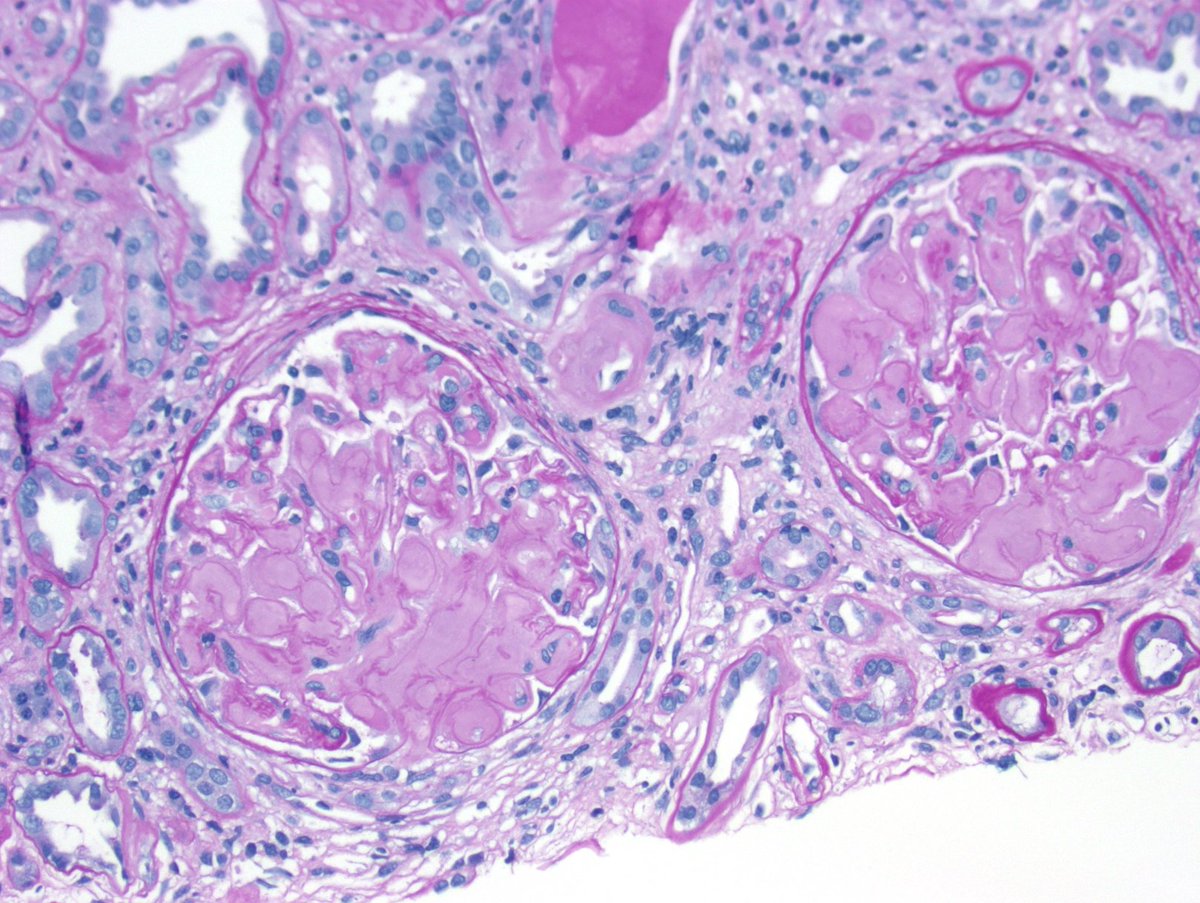

Long weekend often brings urgent cases. Here is one that was STATed, ended up showing anti-GBM GN. Diffuse crescents (nearly 100%). Linear IgG. #RenalPath